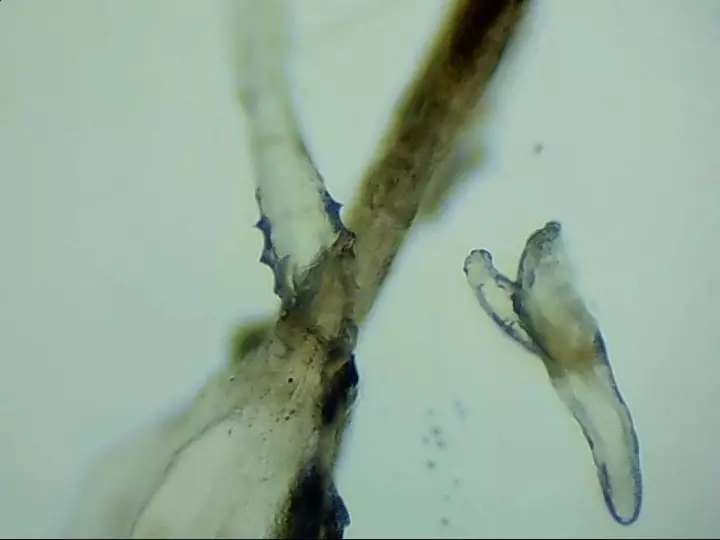

寄生在人體的蠕形螨以毛囊蠕形螨為主,皮脂蠕形螨次之。在眼部,毛囊蠕形螨寄生于睫毛毛囊,而皮脂蠕形螨則分布于睫毛毛囊的皮脂腺和瞼板腺內(nèi)。兩種螨蟲經(jīng)常生活在睫毛和眉毛根部,它們通過生產(chǎn)的卵、排泄的廢物和分泌的分泌物導(dǎo)致過敏反應(yīng),并在人體免疫系統(tǒng)變?nèi)鯐r(shí)引起眼部感染。

蠕形螨性瞼緣炎門診配備有光學(xué)顯微鏡鏡檢、活體激光共聚焦顯微鏡檢查等高新設(shè)備可作出精準(zhǔn)診斷。并有多種治療手段全方面驅(qū)逐、殺死螨蟲。